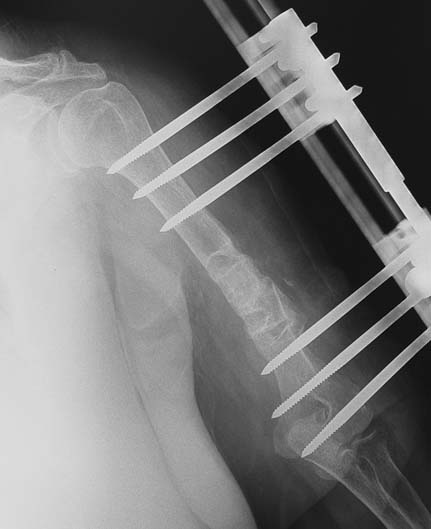

Pseudarthrosis of fracture and pseudarthrosis treatment is currently important problem for orthopedic surgery. Various treatment modalities have been described for pseudarthrosis treatment. All of the treatment methods include high complication rates and additional problems. Leg-length discrepancy, deformity and soft-tissue loss and chronic infection can concomitance with pseudarthrosis. Many internal or external fixation techniques have been described for pseudarthrosis. Debridement and resection of bone fragment from the pseudarhtosis area vascularized or nonvascularized fibula graft, vascularized muscle flaps, bone grafting followed internal fixation techniques make a option for treatment of pseudarthrosis treatment. But these treatment modalities may not correct deformity and leg-length discrepancy. Recently, ilizarov techniques which is basis depend on distraction osteogenesis , bone segment transport or acute shortening after the resection at the site of pseudarthrosis combined with lengthening at another level of bone have been used. These treatment techniques may include some advantage for problems of infection, leg-length discrepancy, soft-tissue loss, and joint contracture.